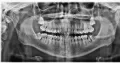

Была на приеме у одного стоматолога, сказал, что нужно удалять нижние восьмерки, одна из них - разрушена. Не больно постучали по нижней левой восьмерке, я выплюнула кусочки зуба. Пошла к другому стоматологу-хирургу, сделала панорамный снимок, сказал, что нужно удалять верхние восьмерки (сказал, что корни целые, но сами зубы - разрушены).

Скажите, пожалуйста, насколько это возможно, какие зубы нужно удалять?